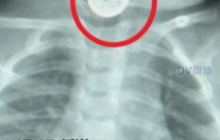

- 广州11月宝宝误吞枕边祈福币险窒息是怎么回事?详情介绍

- 近日,在广东广州,一名仅11个月大的宝宝因误吞硬币被紧急送医。这起事件再次敲响了婴幼儿家庭安全的警钟。幸运的是,在医生的快速处理下,硬币被成功取出,宝宝转危為安。医生也借此机会向广大家长普及了儿童误吞异物的紧急处理知识。